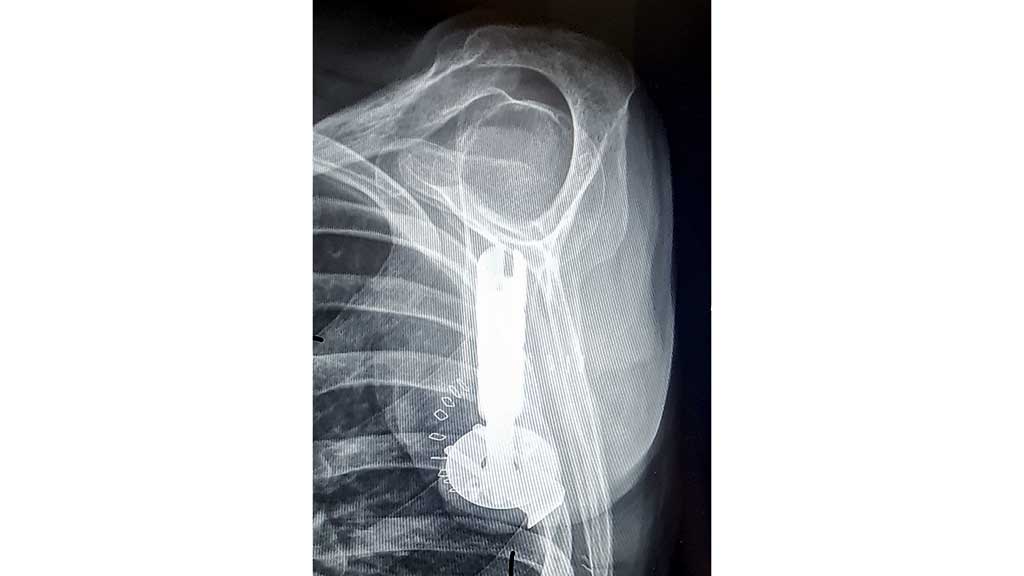

TMR-OP und Step 1 (Abb. 4) der Osseointegration erfolgten am 27.01.2021 in der Universitätsmedizin Göttingen 8. Nach einer Einwachsphase der Fixierung im Humerus und einer Abheilung nach der TMR-OP erfolgte am 23.06.2021 Step 2 der Osseointegration mit der Einbringung des Implantates (Abb. 5) zur späteren Aufnahme für die Prothese, ebenfalls in Göttingen durch das Team aus der Universitätsmedizin Göttingen von der Klinik für Unfallchirurgie, Orthopädie und Plastische Chirurgie, bestehend aus Prof. Dr. med. Frank Braatz, Prof. Dr. med. Gunther Felmerer und Dr. med. Jennifer Ernst sowie mit Unterstützung durch Prof. Rickard Brånemark von der Universität Göteborg in Schweden. Für die Versorgung wurde wie oben erläutert das „OPRA™ Implant System“ von Integrum verwendet.